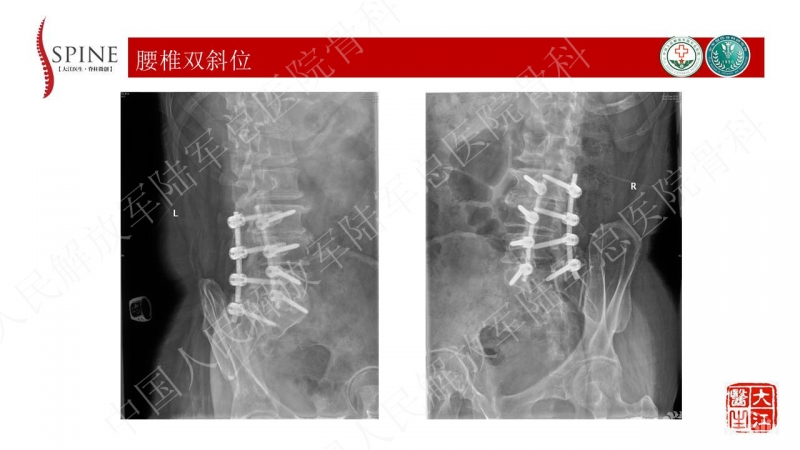

本病例的焦点在患者腰痛的原因,患者明确其腰痛非慢性腰痛,伤后出现。结合病史、体格检查、断棒的表现,主要考虑下腰段的原因。要考虑两个原因,一是腰5-骶1的未融合,断棒后不稳,局部应力集中。二是断棒后局部异常活动,带动瘢痕牵拉硬膜囊及神经根的向背侧牵拉,这种异常活动在残留小关节的抵挡下会引起严重卡压,而出现下肢的疼痛、甚至神经功能损害等。患者行原术区内固定取出,腰5-骶1内固定术,术后取得良好效果,证实患者本次疼痛病因为腰5-骶1节段断棒后应力集中、异常活动。

患者疼痛为伤后出现,不是根性痛表现,而是机械性疼痛,活动及下地时明确。上位节段已融合,考虑到长节段固定后腰5-骶1节段由于杠杆原理出现内固定失败的风险大,术中取出原内固定后,仅行腰5-骶1短节段固定,取得了良好的临床效果。美中不足的是,因椎管内瘢痕粘连重,未重新加强融合,之后需严密随访。